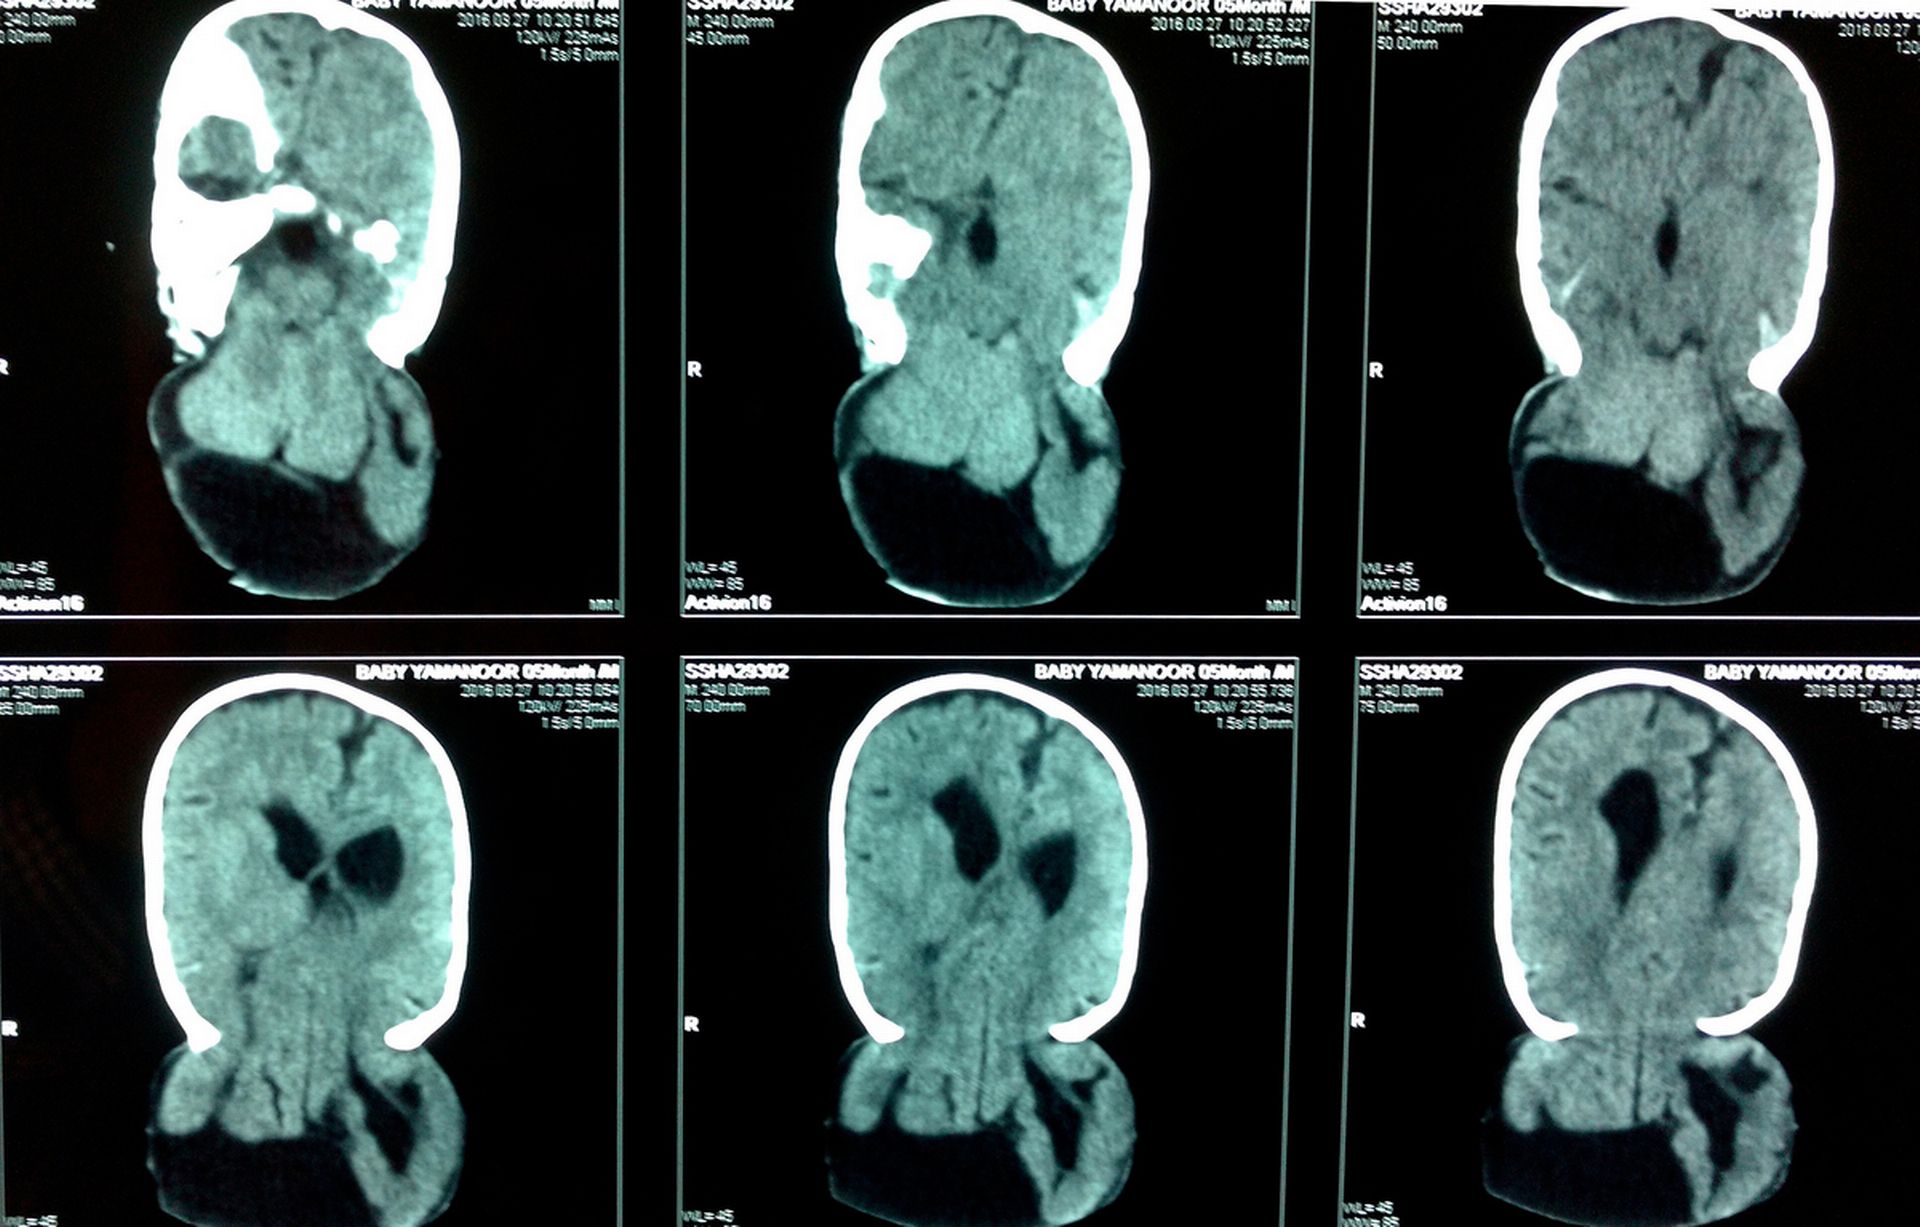

Il 27 marzo, il piccolo è stato sottoposto all’operazione per la rimozione della seconda “testa” e l’intervento è durato quasi 6 ore. Le speranze di successo erano minime perché i bambini piccoli non possono perdere troppo sangue. Un neurochirurgo che si è occupato del caso ha spiegato che il problema di Yamanoor è stato causato dalla mancanza di acido folico nel corpo della madre. Il piccolo è stato dimesso dall’ospedale e le sue condizioni sono buone, anche se ogni 3 mesi dovrà fare dei controlli.